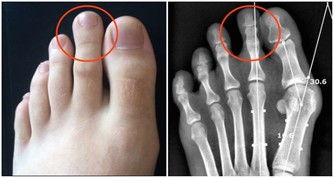

■腿部衰老的8大預警信號

1、腿腳沒有以前靈便了,稍多走點路,就會發酸發脹。

2、用點力或者站的時間稍長,就會腰酸腿疼。

3、步速越來越慢,偶爾走快點,會覺得腿腳不聽使喚。

4、 即使是夏天,也經常會感到小腿肚涼颼颼的,有時還會從臀部一直涼到腳後跟。

5、 抽筋次數增多。

6、雙腿腫脹。

7、 靜脈曲張,腿部血管非常清晰。

8、髖膝關節疼痛,甚至有摩擦磨損、卡住動不了的感覺。